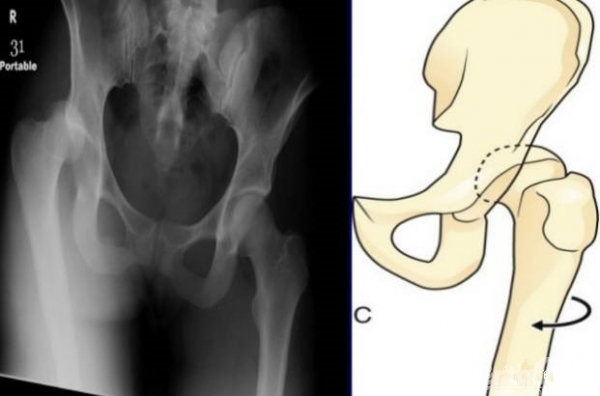

1、将患者健侧的腿完全屈曲,脚后跟尽量接触屁股并且稳定。

2、位于患侧,将胳膊置于患侧下方腘窝处,搭到健侧的膝盖上。

3、右手抓住患者的脚踝,可以进行旋转和内外的控制进行复位。

4、也可以借助肩膀来进行进一步的复位。